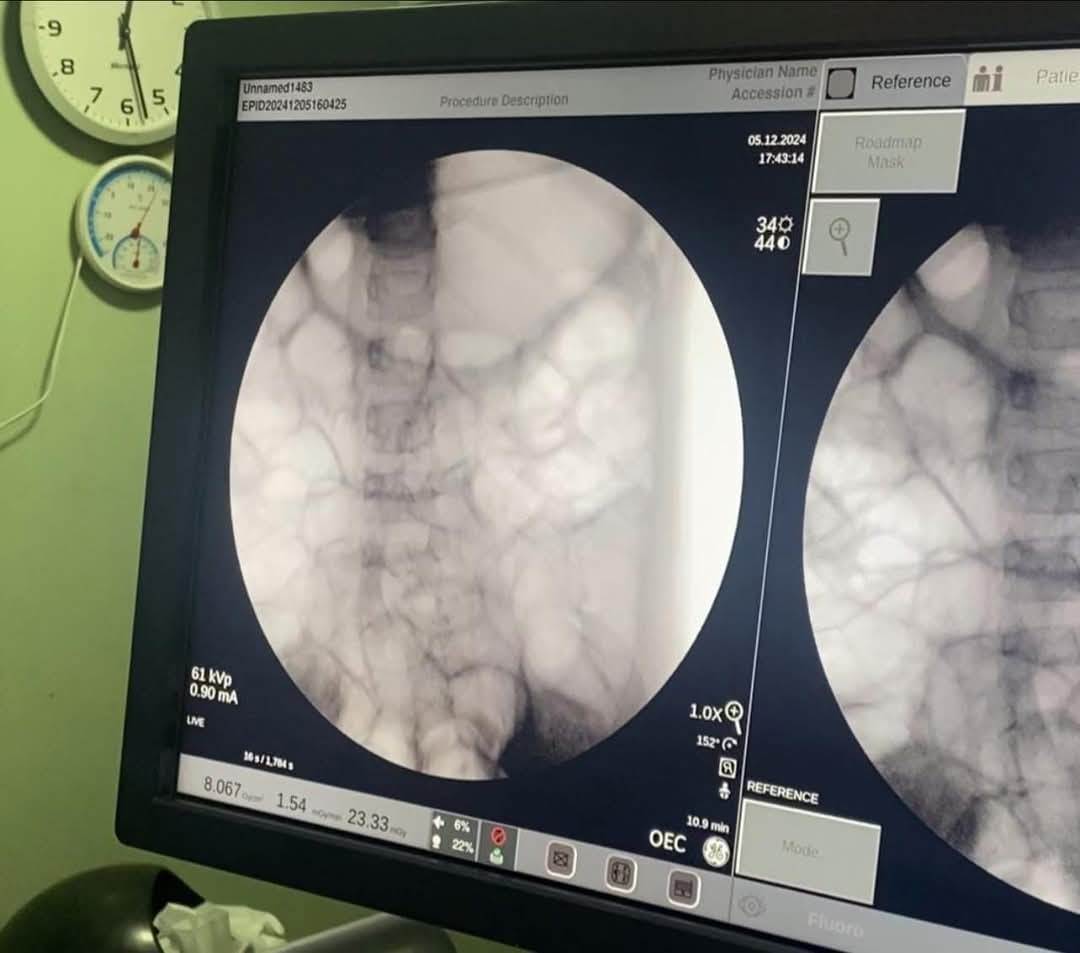

وتم حجز الطفلة فورًا بالمستشفى، وإجراء الفحوصات اللازمة من أشعة وتحاليل، التي كشفت عن وجود جسم غريب داخل المعدة.

وعلى الفور أدخلت الطفلة إلى غرفة العمليات، حيث تم استخراج قطعة معدنية حادة من براية قلم رصاص كانت مغروسة في جدار المعدة، باستخدام منظار الجهاز الهضمي.